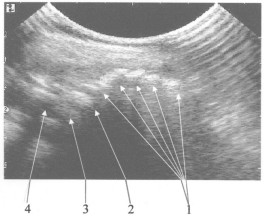

На чертеже представлена сонограмма крестцово-копчиковоо сегмента, получаемая при использовании ультразвукового обследования.

Ребенка укладывают на правый бок. Ноги сгибают в коленях и приводят к передней брюшной стенке. Датчик ультразвукового аппарата помещают в межягодичной складке в проекции крестца перпендикулярно коже в сагиттальной плоскости. Сканирование проводится на частоте 5 MHz, которая обеспечивает достаточную глубину проникновения ультразвуковых волн для визуализации костно-хрящевых структур дистального отдела позвоночника. Датчик постепенно перемещают в каудальном направлении, сохраняя его пространственную ориентацию. Перемещение датчика останавливают, когда на экране визуализируются структуры конечного отдела позвоночного столба: все копчиковые позвонки, представляющие собой на сонограмме гиперэхогенные зоны 1, последний крестцовый позвонок, представляющий собой гиперэхогенную зону большего размера 2, который отделяется от места окончания спинно-мозгового канала соединительнотканной прослойкой 3, которая выглядит как эхоположительная зона меньшей интенсивности, чем от последнего крестцового позвонка, спинно-мозговой канал 4, характеризующийся гипоэхогенной зоной и место его окончания. После этого считают количество копчиковых позвонков на сонограмме, которое имеется у больного, и во время операции после выделения последнего копчикового позвонка отсчитывают в краниальном направлении то число позвонков, которое получено на сонограмме, и прибавляют еще один, которым является последний крестцовый позвонок. Место резекции крестцово-копчикового сегмента должно проходить на границе между соединительнотканной прослойкой, отделяющей место окончания спинно-мозгового канала от последнего крестцового позвонка, и последним крестцовым позвонком, это соответствует краниальному (верхнему) краю последнего крестцового позвонка, что исключает вскрытие просвета спинно-мозгового канала.